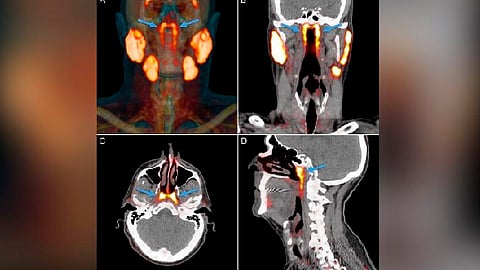

Los investigadores descubrieron nuevas glándulas durante una exploración para buscar tumores, tras escaneos en la cabeza y el cuello a 100 personas vivas, además de diseccionar dos cadáveres, encontraron dichas glándulas en todos los participantes de la investigación.

Supuestamente, estas glándulas no fueron descubiertas con anterioridad debido a que no se pueden ver con métodos convencionales como un ultrasonido, tomografías o resonancia magnética, sólo pueden visualizarse con un nuevo tipo de exploración llamado PSMA PET/CT que se utiliza para la propagación del cáncer de próstata.